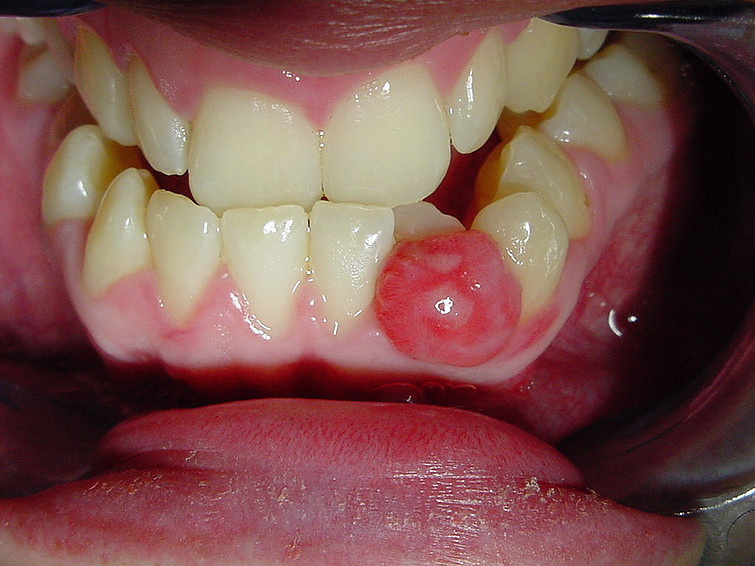

Central giant cell granuloma. Central giant cell granulomas are benign lesions that grow from bone cells. They most often occur in the front portion of the lower jaw. One type of these tumors can grow rapidly, cause pain and destroy bone, and has a tendency to recur after surgical treatment. The other type is less aggressive and may not have symptoms. Rarely, a tumor may shrink or resolve on its own, but typically these tumors require surgical treatment.